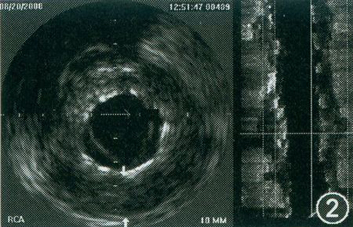

退出后复查造影:前降支支架近端及远端可见10%的残余狭窄,经指引钢丝送SPRINTER 2. 50 mmx20 mm球囊至前降支内支架远端及近端,分别以18个大气压x5s、20个大气压x5s后扩张2次,复查造影:支架内无残余狭窄,未见血栓形成及内膜撕裂,前向血流TIMI 3级。最后对右冠状动脉进行血管内超声检查,结果显示存在支架贴壁不良,右冠状动脉支架的远端可见支架部分断裂,部分支架支撑外血管管腔扩大(图1、2)。3年前在前降支置入支架的重叠部分近段也存在支架断裂(图3)。

图2 血管内超声显示支架与血管外弹力膜之间距离较大,其间可见到血液斑点,支架支撑点消失,存在支架断裂

本例患者血管内超声可以清楚地看到右冠状动脉局部外弹力膜扩大,并且在支架支撑和外弹力膜之间可清楚地见到血流斑点。由于3年前没有行血管内超声检查,因此不能确定是持续性贴壁不良还是晚期贴壁不良。但从造影结果可知,当时右冠状动脉并没有支架局部血管扩张,因而我们还是倾向于诊断患者为晚期支架贴壁不良。